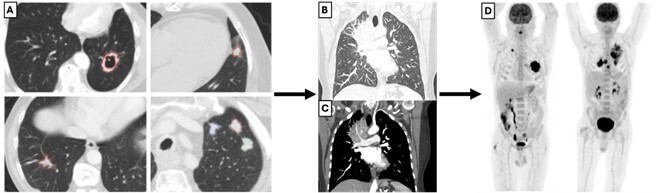

Lorsqu’ils sont détectés par imagerie, les nodules de moins de 6 mm ne sont pas suivis chez les patients à bas risque (non-fumeurs). Pour les nodules mesurant entre 6 et 8 mm, une TDM de contrôle est réalisée à six-douze mois. Enfin, une TEP-TDM au FDG (ou un scanner ou une biopsie) est indiquée pour les nodules pulmonaires solitaires solides de plus de 8 mm de diamètre (selon les guidelines de la Fleischner Society) avec de bonnes performances pour différencier les lésions bénignes et malignes.12 Un exemple de nodules pulmonaires solitaires solides visualisés sur la TDM thoracique et une TEP-TDM au FDG de suivi est présenté  en figure 3. La détection peut cependant être limitée par des faux positifs et négatifs dus à des facteurs techniques ainsi qu’aux éventuelles infections ou inflammations intercurrentes.

Un patient de 65 ans, ancien fumeur avec un antécédent d’hypertension artérielle bien contrôlée, consulte pour une toux persistante. Une tomodensitométrie (TDM) révèle un nodule pulmonaire solitaire solide de 9 mm de diamètre. Il lui est ensuite recommandé de réaliser une tomodensitométrie par émission de positons (TEP-TDM) au fluorodésoxyglucose (FDG).

Pourquoi ?

Selon les recommandations de la Fleischner Society, pour un nodule pulmonaire solitaire solide de plus de 8 mm, il est recommandé de réaliser une TEP-TDM au fluorodésoxyglucose pour le caractériser, puis une biopsie ou un contrôle par TDM à trois mois, aussi bien chez les patients à faible qu’à haut risque.12